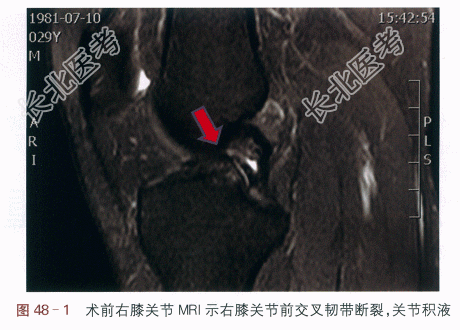

(1)术前MRI:右膝关节前交叉韧带断裂,关节积液,如图48-1所示。

(2)关节镜下所见:前交叉韧带前内侧束、后外侧束完全从中段断裂,两侧残端均未吸收。行前抽屉试验可见胫骨相对于股骨向前位移增大,前交叉无生物力学作用。